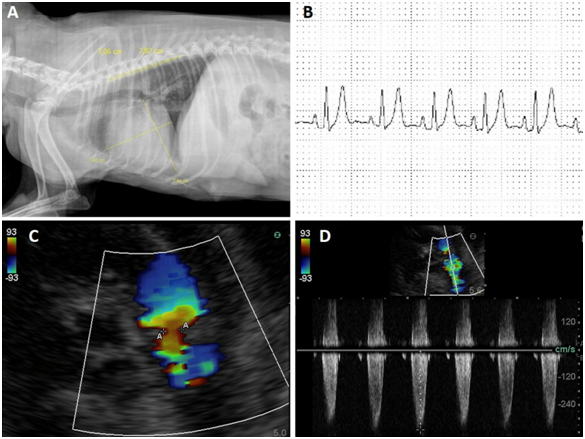

The animal was hospitalized and complementary exams such as, thoracic radiography, electrocardiography, echocardiography, abdominal ultrasonography, hemogram and biochemicals were requested. In the hemogram, no abnormalities were found, whereas in the biochemical, there was a decrease in urea and globulin levels and an increase in creatine kinase. Radiographic examination showed an increase in the cardiac silhouette, with loss of definition of the cardiac apex, globose heart, pleural effusion and generalized cardiomegaly (Figure 1A). Abdominal ultrasonography revealed free fluid and thick floating septations with hyper refrigerant echoes. The electrocardiographic examination excluded the presence of arrhythmias and demonstrated findings consistent with atrioventricular overload and myocardial hypoxia (Figure 1B).

Figure 1 A: Radiographic examination showed an increase in the cardiac silhouette, with loss of definition of the cardiac apex, globose heart, pleural effusion and generalized cardiomegaly.

B: The electrocardiographic examination excluded the presence of arrhythmias and demonstrated findings consistent with atrioventricular overload and myocardial hypoxia.

C-D: Note the stenosis and pulmonary valve insufficiency, with a regurgitant flow of 26 mmHg mild pulmonary hypertension.

7. Stenosis and pulmonary valve insufficiency, with a regurgitant flow of 26 mmHg mild pulmonary hypertension (Figure 1C-1D).

Echocardiography was very sensitive in the identification of stenosis, as well as in the determination of pulmonary flow velocities and areas of greater turbulence, characterized by color mosaic and spectral waves with absence of systolic window and notches during the wave deceleration phase. The lesion was identified at the valve level, where a blood flow velocity of 201.9cm/s and pressure gradient (GrP) of 26mmHg, mild grade stenosis, was determined. Such alterations are similar to echocardiographic findings in human PD patients, in which pulmonary stenosis, right ventricular hypertrophy, reduced RV systolic function, biatrial enlargement, aortic insufficiency, mitral and tricuspid insufficiency and shunts were reported. However, the severity of these varied changes in each case according to the degree of the change and the presence of other pathologies.15,23